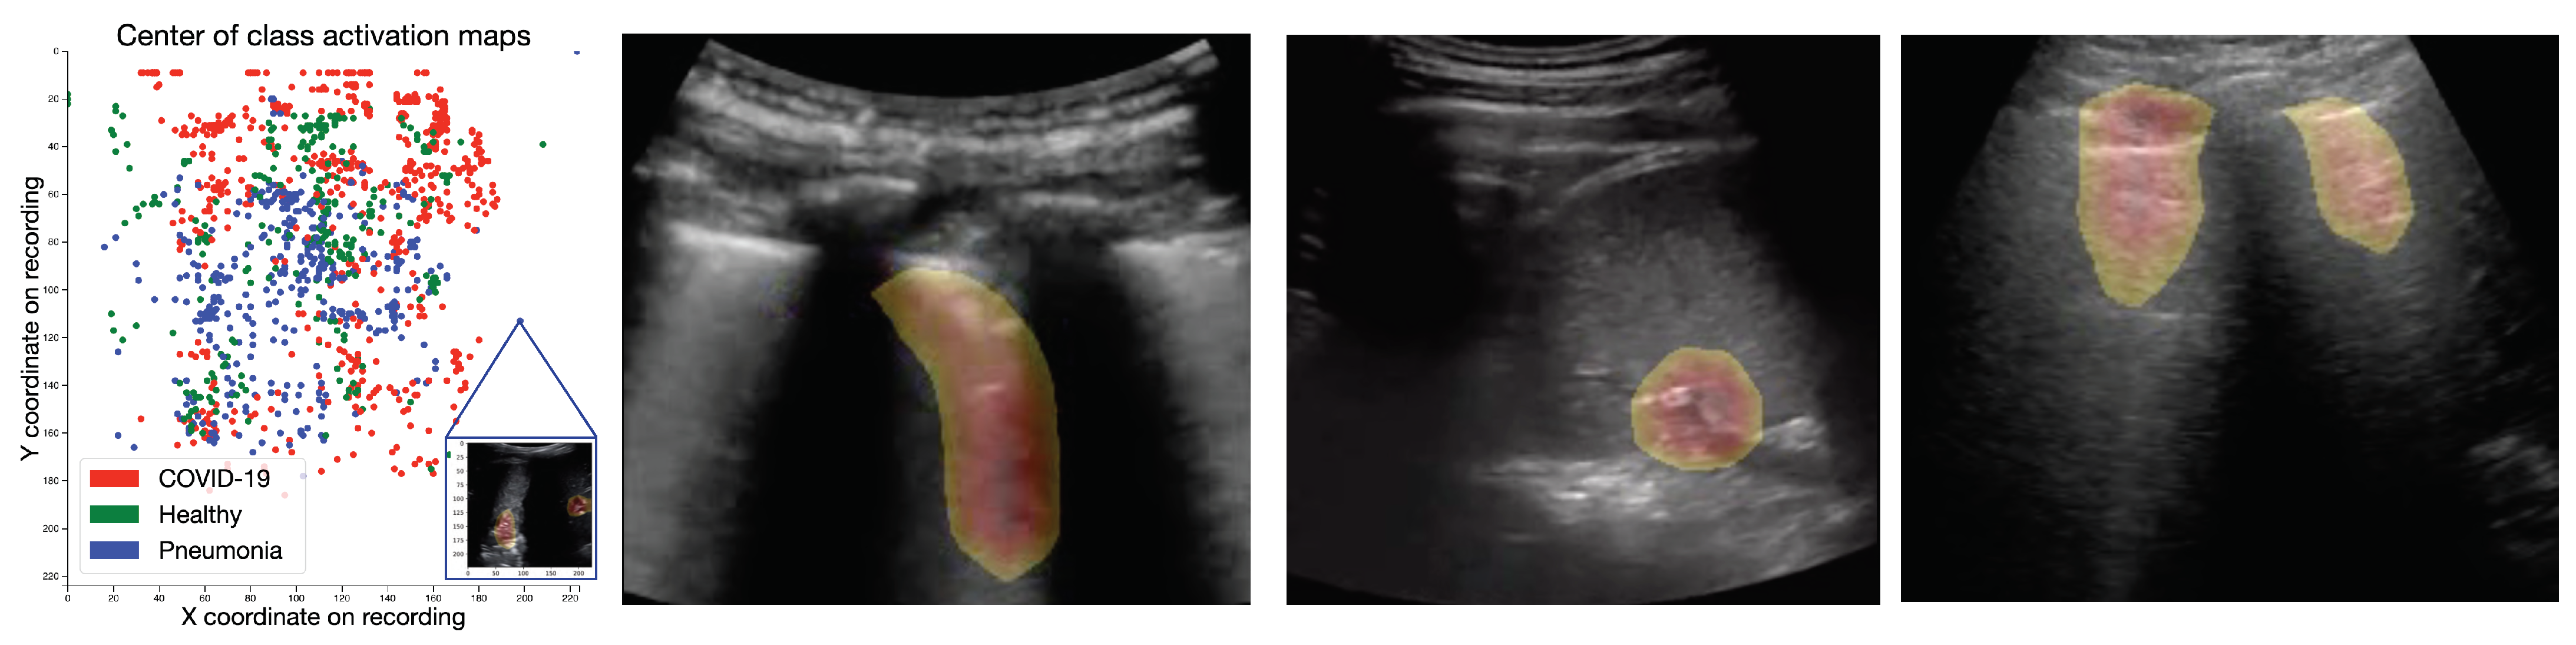

Figure 5 shows representative CAMs in the three rightmost panels. They highlight the most frequent US pattern for the three classes, COVID-19 (vertical B-lines), bacterial pneumonia (consolidations), and healthy (horizontal A-line). For a more quantitative estimate, we computed the points of maximal activation of the CAMs for each class (abbreviated as , , and ) and all samples of the dataset (see Figure 5 left). While, in general, the heatmaps are fairly distributed across the probe, pneumonia related features were rather found in the center and bottom part, especially compared to COVID-19 and healthy patterns. Please refer to Appendix D for a density plot. The interactive HTML and a few exemplary CAM videos are available as Supplementary Material: https://bit.ly/2HH4sUt To assess to what extent the differences between the individual distributions are significant, we employed maximum mean discrepancy (MMD), a metric between statistical distributions [76] that enables the comparison of distributions via kernels, that is, generic similarity functions. Given two coordinates and a smoothing parameter , we use a Gaussian kernel to assess the dissimilarity between x and y. Following [76], we set to the median distance in the aggregated samples (i.e., all samples, without considering labels). We then calculate MMD values for the distance between the three classes, that is, , , and . Repeating this calculation for 5000 bootstrap samples per class (see Figure A5 for the resulting histograms), we find that the observe achieved significance levels of the intra-class MMD values of well below an significance level.

Figure 5.

Class activation maps. (Left): Interactive scatterplot of the origins of the CAMs across the entire dataset, colored by class. While the data seems rather unstructured, pneumonia-CAMs have lower y-coordinates than COVID-19 and healthy samples. (Rest): Exemplary CAMs for COVID-19 (highlighting a B-line), bacterial pneumonia (highlighting pleural consolidations) and healthy lungs (highlighting A-lines).